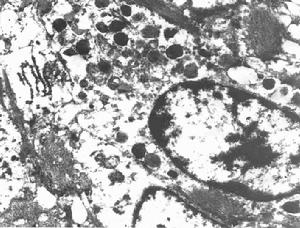

此瘤系由惡性神經鞘細胞和神經膜細胞組成,包膜常不完整,大都有瘤細胞浸潤。瘤細胞呈梭形,浸潤性生長,排列成交織條索狀,有時呈羽毛狀,偶或呈柵欄狀或網狀結構,伴有出血和壞死灶。瘤細胞核呈卵圓或梭形,有些為多邊形,大小不一,有明顯異型,有時見巨核或多核。核有絲分裂象多見。